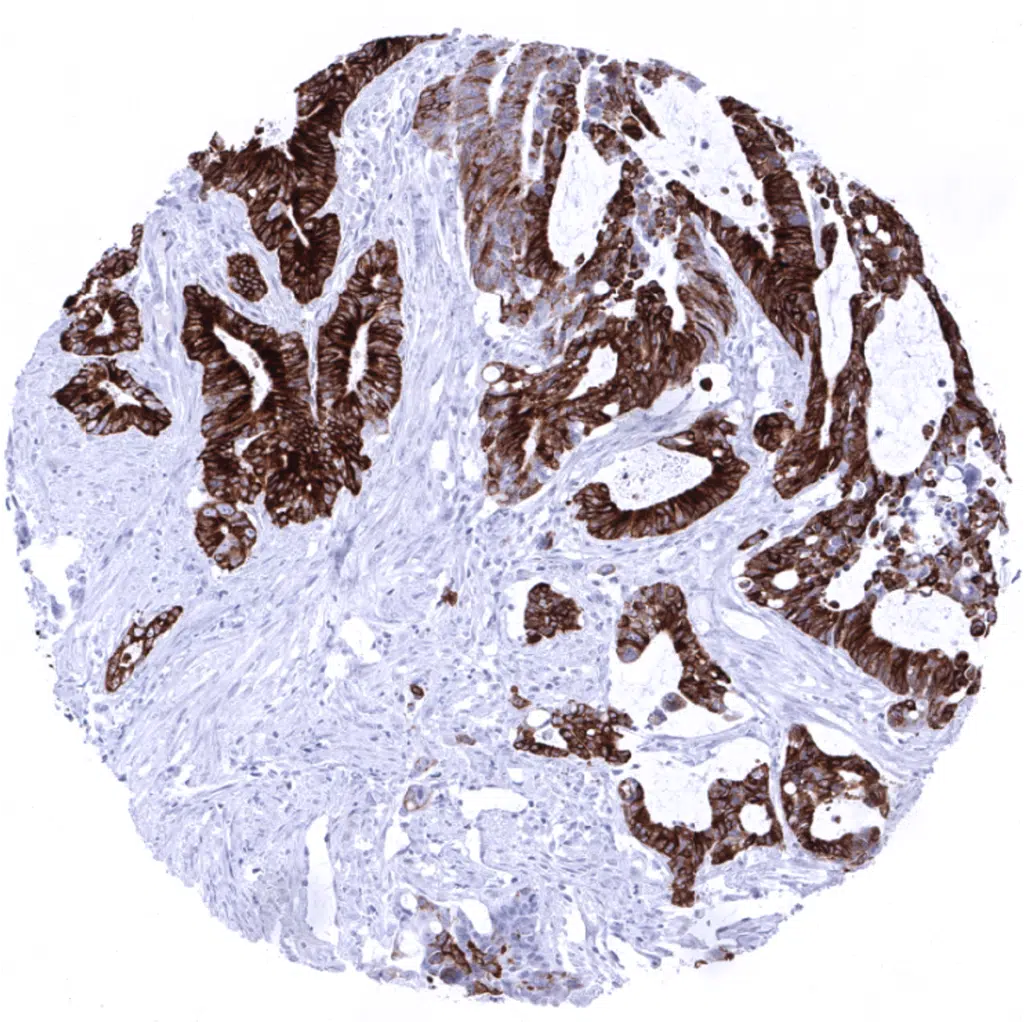

Colon- Colorectal adenocarcinoma containing areas with diffuse MUC5AC positivity next to areas with rather few interspersed MUC5AC positive cells.